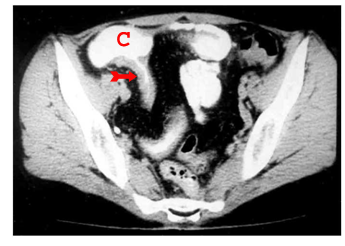

האבחון הרנטגני הוא חשוב. צילום בליעת בריום, אנטרוקליזיס וטומוגרפיה ממוחשבת של הבטן עם בליעת חומר ניגוד הם הכלים העיקריים לאבחנה. קשת של סימנים מצביעה על פתולוגיה במעי הדק.

- הדופן מעובה, ולכן המרחק בין הלולאות הוא רב (תצלום 15.5).

- נצורים אפשר להדגים בחלק מהמקרים (תצלום 19.4)

המנגנון של התהוות נצורים אלה הוא התכייבות דלקתית הדרגתית, החודרת דרך כל שכבות דופן המעי הנגוע. התהליך הדלקתי ההדרגתי (להבדיל מהתנקבות חדה, שאינה שכיחה, כאמור) גורם להידבקות המעי המודלק אל איבר אחר בחלל הצפק או אל דופן הבטן. המשך התהליך הדלקתי גורם לחדירה אל נהור האיבר הסמוך או לפריצה אל פני שטח הגוף (תצלום 20.4).